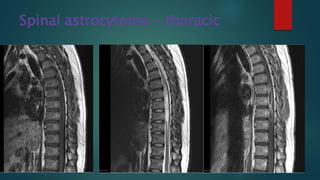

Spinal astrocytoma - thoracic

• #67 T2 hyperintense expansion of the thoracic cord is demonstrated. The main mass effect is centred  between T5 and T8 but abnormal high T2 signal extends between T4 and T11. Postcontrast images demonstrate patchy irregular peripheral enhancement of this lesion, and central low intensity.  No definite evidence of blood products/haemorrhage although some T2 hypointensity is seen.No further intra medullary lesion is identified.